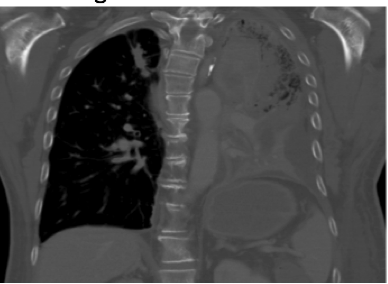

Let me give an example. Mitochondria divide when cell’s divide. Cell division is called mitosis. While some mitosis (cell division) is good-too much is bad. Too much mitosis is a key feature of lung cancer and is also seen in blood vessel diseases, such as pulmonary arterial hypertension (PAH). In developing therapies for lung cancer and PAH, most scientists have focused on the importance of division of the nucleus, which gives the daughter cells an equal share of genetic material. My lab has instead chosen to focus on the role of mitochondrial dynamics in supporting increased rates of mitosis that are key to both lung cancer and PAH. Lung cancer is a disease of excessive cell growth and impaired apoptosis. It has a high mortality rate despite modern treatment and usually is already advanced when it presents. The most common form is called non-small cell lung cancer (see CT scan below).

Non-small cell lung cancer (seen in the left lung on the CT scan above) has a median survival of only 1 year, despite therapy.